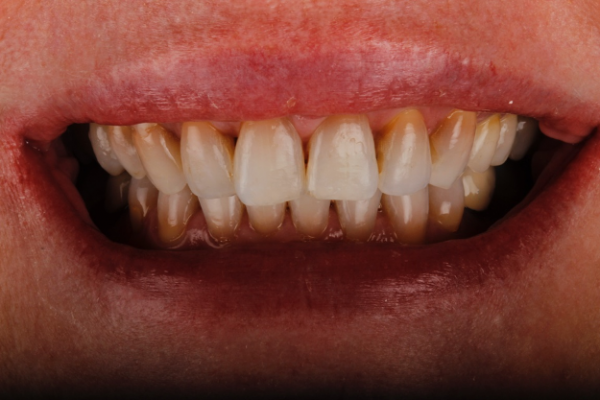

In the case shown, (Figure 1a) the patient wanted her teeth to be completed prior to her wedding in 14 weeks from the time she presented. She also requested a material with the longest performing clinical lifespan.

If all of these considerations are taken into account with this case, we can see that the upper right central incisor would be subject to significant tooth reduction (Figures 1b and 1c) and the risk of iatrogenic pulpal death would be increased. Even with immediate dentine sealing and other protective practices adopted.